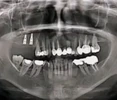

Diş Çürükleri

Diş Eksikliği

Periimplantitis

Peri-İmplant Mukozitis

Çene Kistleri

Implant tedavisi